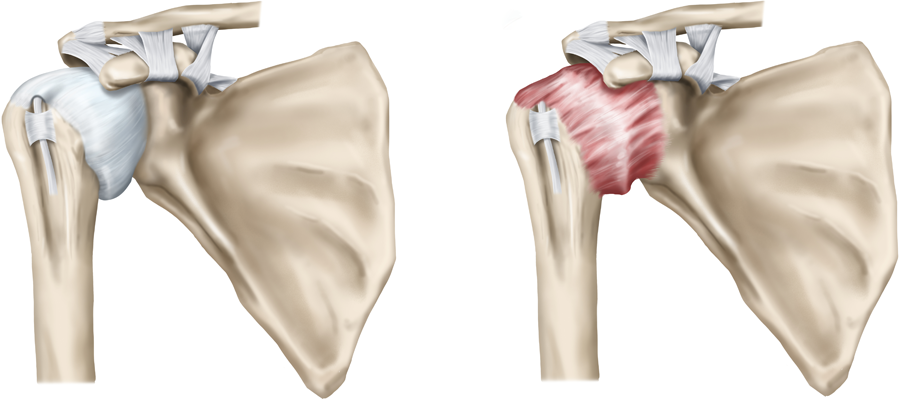

- 회전근개 파열

- 어깨뼈 사이에 위치한 4개의 근육(회전근개) 중 하나 이상이 끊어지거나 손상된 상태입니다.

- 정의: 어깨 내 회전근개(4개의 근육 힘줄) 중 하나 이상이 끊어지거나 손상된 상태입니다.

- 증상: 팔을 위로 올릴 때 통증이 심하고, 마찰음이 들릴 수 있습니다.

- 팔을 들어 올린 채 10초 이상 유지하기 힘들며, 밤에 통증이 악화하는 경향이 있습니다.

- 스스로 팔을 올리지 못해도, 다른 사람이 들어주면 팔이 올라갑니다.